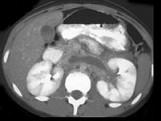

男,48岁,蛋白尿多年,CT如图所示,诊断为肾静脉血栓,肾静脉血栓形成的原因 ( )A.膜性肾小球肾炎B.肾癌C.胰腺炎D.外压性...

问题 男,48岁,蛋白尿多年,CT如图所示,诊断为肾静脉血栓,肾静脉血栓形成的原因 ( )

选项 A.膜性肾小球肾炎 B.肾癌 C.胰腺炎 D.外压性 E.创伤、脱水、血小板增多症

答案 ABCDE